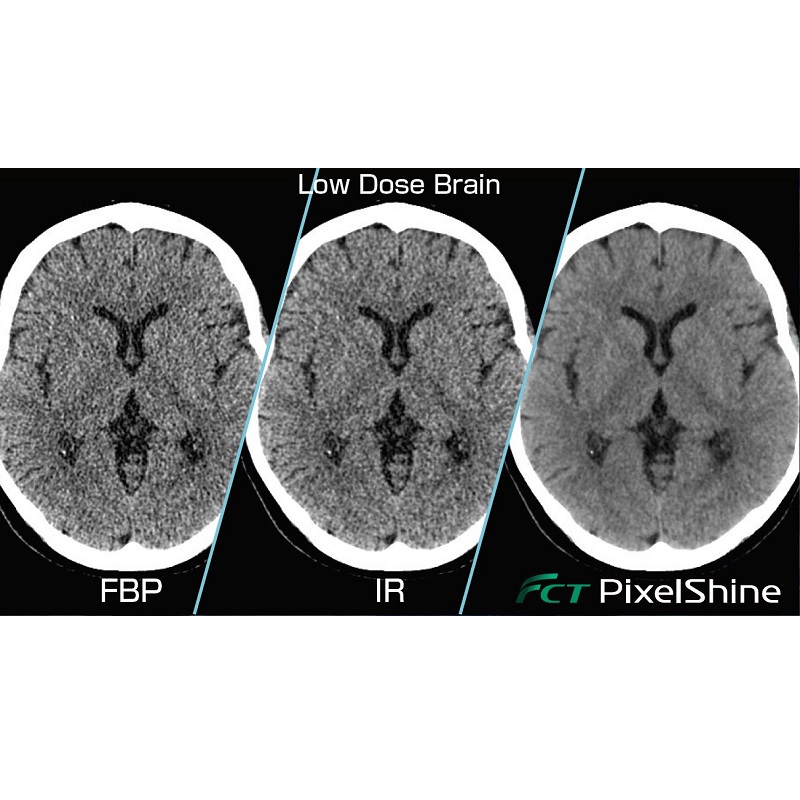

- FCT PixelShine – Sztuczna inteligencja (AI) oparta na technologii “Deep Learning” umożliwia otrzymanie wysokiej jakości obrazy diagnostyczne z nisko dawkowej techniki obrazowania.

Technologia sztucznej inteligencji wykorzystana do nauki FCT PixelShine i poprawy rekonstrukcji obrazów TK o niskiej dawce. W trakcie tworzenia FCT PixelShine otrzymał ogromna liczbę zaszumionych par obrazów TK o niskiej i wysokiej jakości. FCT PixelShine uzyskał umiejętność mapowania, miedzy obrazami z szumem o niskiej dawce, a odpowiadającymi im obrazami w wysokiej jakości ze standardową dawką promieniowania.